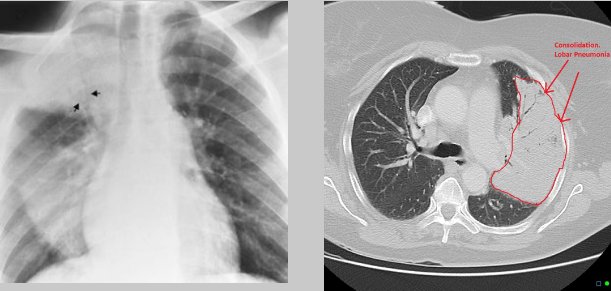

Describe the RA for alveolar pneumonia (this pic and pic in description)

homogenous consolidation in segments or the entire lung — air bronchograms are present (when an entire lobe fills with fluid but has not collapsed)

PT is 43 yr old male presenting with productive cough and fever/chills

What pathology is present?

pneumonia — alveolar/pneumococcal pattern